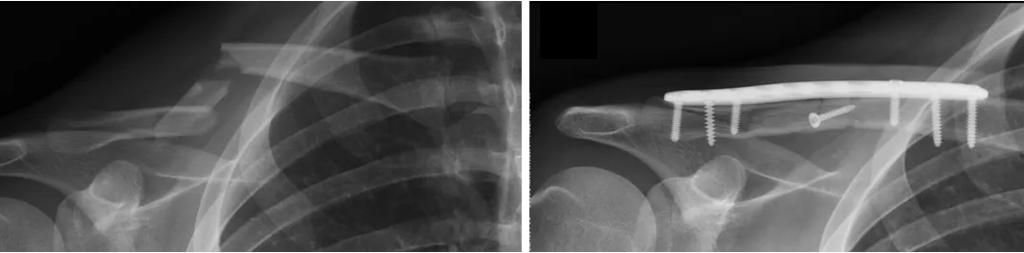

Fratura da Clavícula

A fratura da clavícula é frequente, e mais comum em crianças e adultos jovens. Pode ocorrer após traumas diretos na região, ou em quedas ao solo.